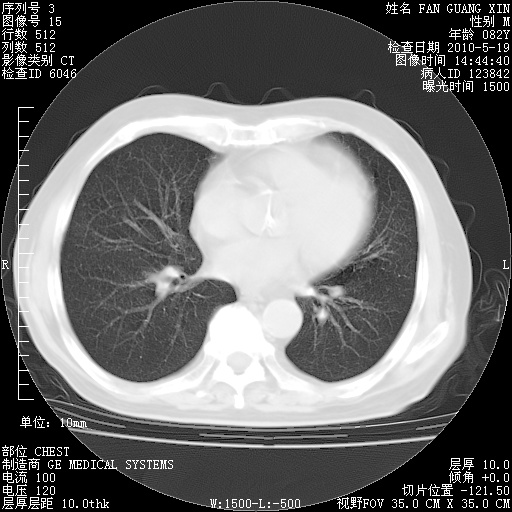

复查肺部CT,明显好转。为什么发热呢?

治疗3周后的肺部CT

治疗3周后的肺部CT纵隔窗